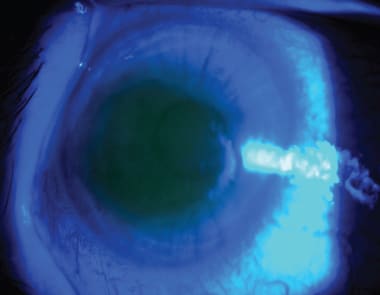

The traditional CXL method involves removing the central 6mm to 8mm of corneal epithelium to allow the large riboflavin molecule to penetrate into the corneal stroma (Figure 1). The epithelium can be removed by methods similar to surface ablation including mechanical scrape, alcohol scrape, laser ablation, or Amoil's brush following a drop of topical anesthetic. A drop of 0.1% riboflavin is instilled into the patient's eye every two minutes for 30 minutes or until the riboflavin is observed to fluoresce in the anterior chamber, indicating full stromal penetrance. Next, 3.0mW/cm2 of UV light (370nm) is applied for 30 minutes (Figure 2), with additional drops of riboflavin instilled every two minutes. A bandage contact lens is applied to the eye, and a postoperative regimen similar to that for photorefractive keratectomy (PRK) is initiated, including a fourth-generation fluoroquinolone and a steroid drop. The bandage contact lens is removed once the epithelium is healed, and topical steroids are continued for four to 12 weeks.

Figure 1. Riboflavin within cornea of a patient undergoing CXL. COURTESY OF DR. ERIC DONNENFELD.